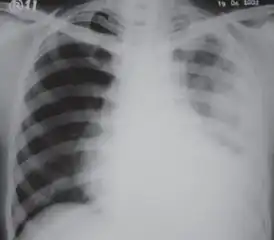

A fibrothorax can typically be diagnosed by taking an appropriate medical history in combination with the use of appropriate imaging techniques such as a plain chest X-ray or CT scan.[1] These imaging techniques can detect fibrothorax and pleural thickening that surround the lungs.[11] The presence of a thickened peel with or without calcification are common features of fibrothorax when imaged.[1] CT scans can more readily differentiate whether pleural thickening is due to extra fat deposition or true pleural thickening than X-rays.[1]

If a fibrothorax is severe, the thickening may restrict the lung on the affected side causing a loss of lung volume.[11] Additionally, the mediastinum may be physically shifted toward the affected side.[1] A reduction in the size of one side of the chest (hemithorax) on an X-ray or CT scan of the chest suggests chronic scarring.[9] Signs of the underlying disease causing the fibrothorax are also occasionally seen on the X-ray.[9] A CT scan may show features similar to those seen on a plain X-ray.[11] Lung function testing typically demonstrates findings consistent with restrictive lung disease.[9]

Extensive left-sided fibrothorax -

Chest radiograph displaying inhomogeneous opacification of the left half of the chest that is fibrothorax -